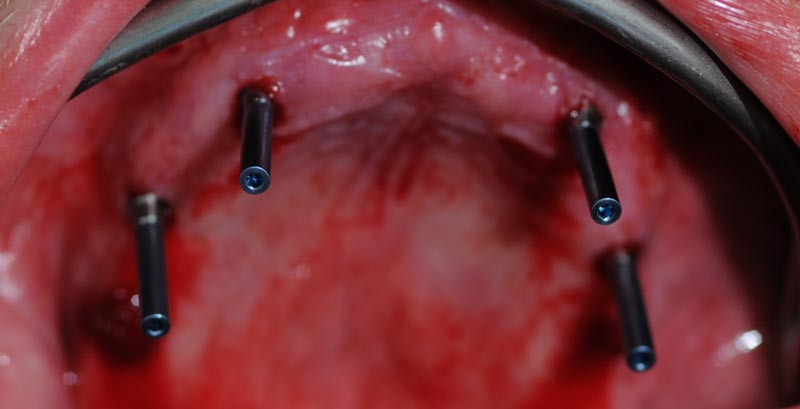

Impianti posizionati

Posizionamento dei MUA negli impianti in base alla posizione progettata